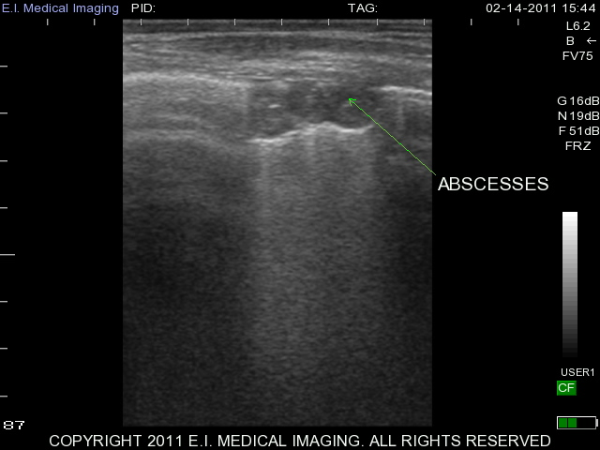

My name is Elizabeth Adams and I am a dairy practitioner in the central valley of California. Recently, I was able to use the IBEX PRO portable ultrasound to look at calf lungs for evidence of damage from calfhood pneumonia. In veterinary school, I scanned all of my patients with respiratory symptoms because it is a fast, non-invasive exam that provides a lot of information quickly. With ultrasound I can see healthy lungs, pleural effusion, atelectasis, consolidation and abscessation.

Ultrasound allows me to look at the surface of the lung; in a healthy lung, this is all we can see as the lung is full of air and doing its job. In a diseased lung, the surface of the lung is abnormal and allows penetration of the ultrasound waves deep into the lung parenchyma. Young calves require only the penetration of a 5-7.5MHz rectal ultrasound probe to see the evidence of damage from previous pneumonia.

It is very important to take measures to prevent calfhood pneumonia and to recognize and treat the disease early. With all of our preventative measures, there will always be some animals that develop a chronic pneumonia. If calves are sent to a custom calf raiser, the client may not know which of his animals have been treated multiple times for pneumonia. As feed costs continue to rise, I believe it is important to make wise investments when selecting animals.